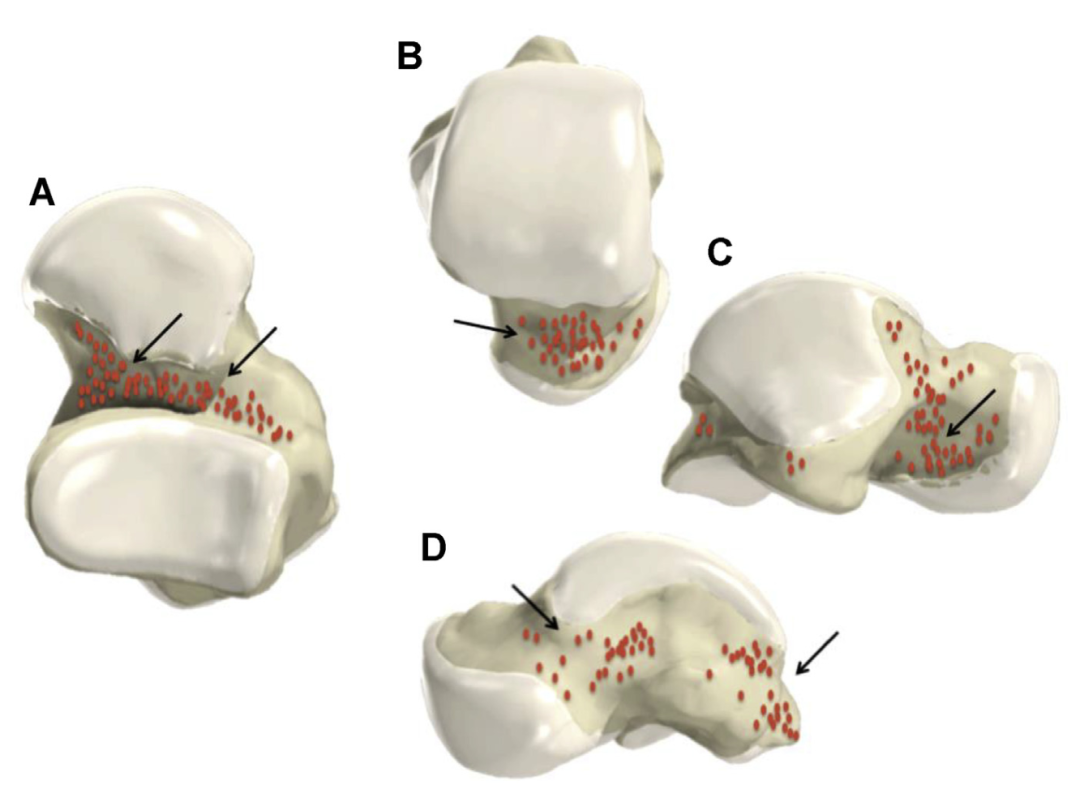

有 頭骨有 骨折有 桡骨远端骨折的治疗策略和入路选择-有 好医术文章-有 好医术-赋能医生守护生命有 桡骨远端骨折的治疗策略和入路选择-有 好医术文章-有 好医术-赋能医生守护生命有 男家中跌倒竟釀「手肘恐怖三聯症」!醫示警8大併發症:恐神經受損|Uho優活健康網有 距骨颈骨折:选单入路还是双入路?(附详细手术步骤)有 -有 上海开为医药科技有限公司--创伤、肢体矫形技术解决方案的专业服务商有 距骨颈骨折:选单入路还是双入路?(附详细手术步骤)有 -有 上海开为医药科技有限公司--创伤、肢体矫形技术解决方案的专业服务商有 有 有